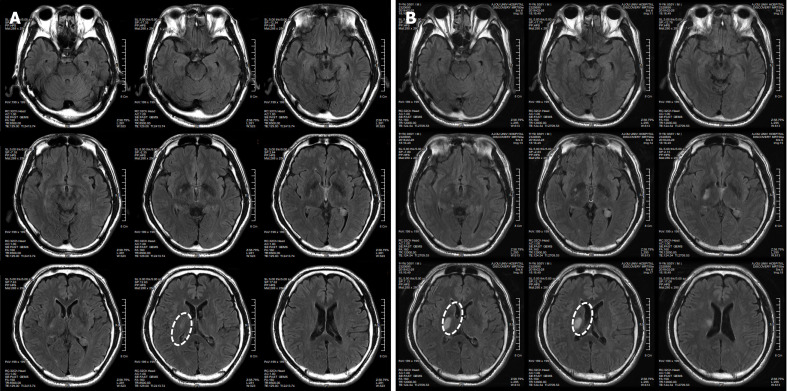

患者于2018年2月17日至18日出現(xiàn)暫時性無力癥狀,早上醒來后突發(fā)急性中風(fēng),導(dǎo)致左上肢和下肢癱瘓。患者在大學(xué)醫(yī)院急診室被診斷為Rt紋狀體囊性梗死(圖1A)。他于2018年3月2日出院,僅接受了阿司匹林處方,因為根據(jù)腦計算機(jī)斷層掃描 (CT) 掃描,他的腦血管正常,盡管他的病情在住院期間惡化(圖1)。出院當(dāng)天,他被送往康復(fù)專科醫(yī)院接受長期康復(fù)治療。然后他于2018年3月13日來韓國首爾生物美容與健康公司 (bBHC)-干細(xì)胞治療與研究所 (STRI)接受干細(xì)胞治療。